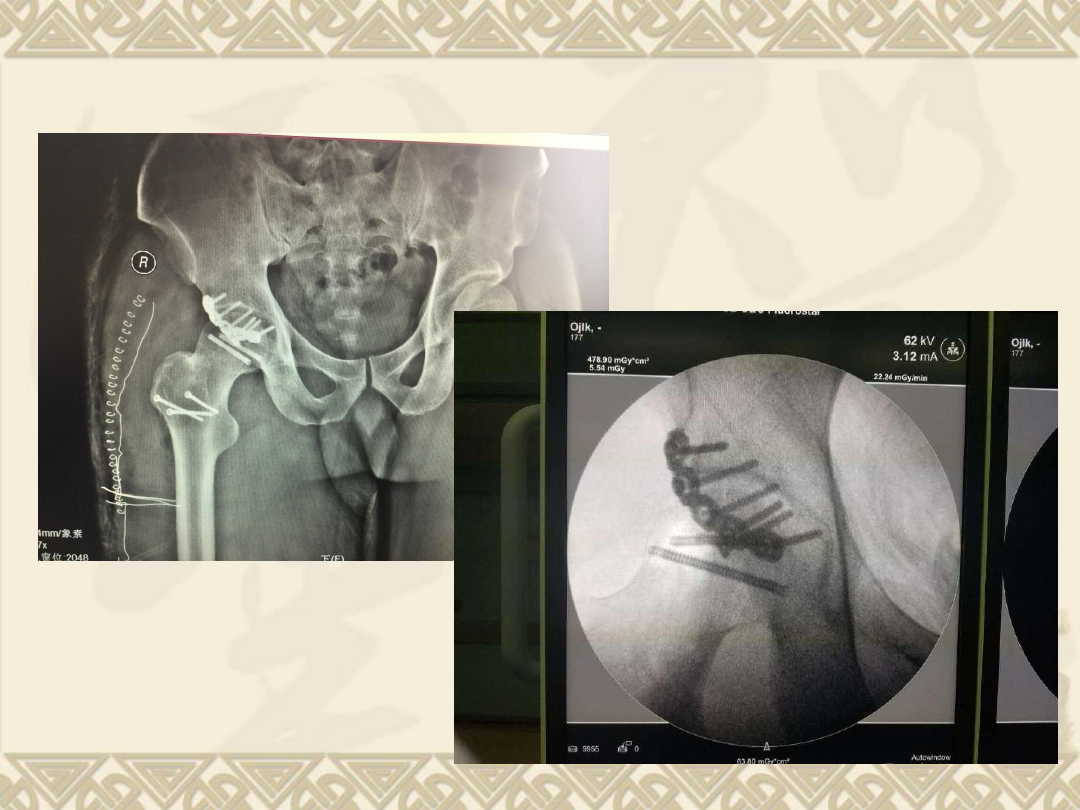

术后资料

background image

v

将臼内股骨头残端取出

复位骨折,

3

枚埋头钉固定

复位髋关节

最后处理后缘骨折,复位后,钢板螺钉固定。